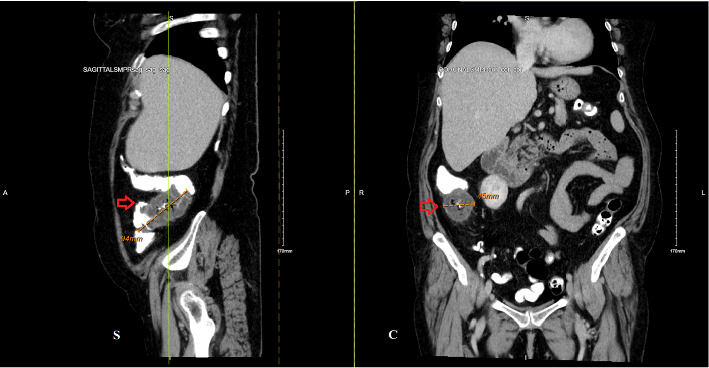

本病例报告描述了一例罕见的非甾体抗炎药(NSAID)诱导的局灶性结肠肉芽肿肿块,类似恶性结肠肿块。它强调了非甾体抗炎药相关胃肠道并发症的诊断挑战,并强调了在类似的表现中考虑这些原因的重要性。及时识别和停用非甾体抗炎药可以防止不必要的手术干预,并促进症状的缓解。本病例强调了详细用药史和谨慎使用非甾体抗炎药以减少不良胃肠道反应风险的价值。

This case report describes a rare occurrence of nonsteroidal anti-inflammatory drugs (NSAID)-induced focal colonic granulomatous mass mimicking a malignant colonic mass. It highlights the diagnostic challenges of NSAID-related gastrointestinal complications and stresses the importance of considering such causes in similar presentations. Prompt recognition and withdrawal of the offending NSAID can prevent unnecessary surgical intervention and facilitate symptom resolution. This case underscores the value of a detailed medication history and cautious NSAID use to reduce the risk of adverse gastrointestinal effects.